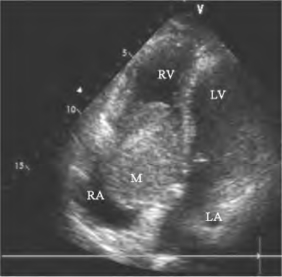

图15-2 右房黏液瘤二维超声图

心尖四腔见右房黏液瘤舒张期进入三尖瓣口,瘤体伸长呈长圆形或舌状(M)。RA右房